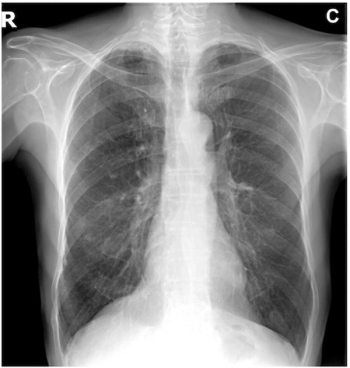

The AI-powered AZchest CXR software reportedly offers 93.79 percent sensitivity and a 98.57 percent AUC for pneumothorax.

Adjunctive use of the AI-powered software led to an average 38.6 percent increase in the detection of pneumothorax by general radiologists, according to a 2023 study.